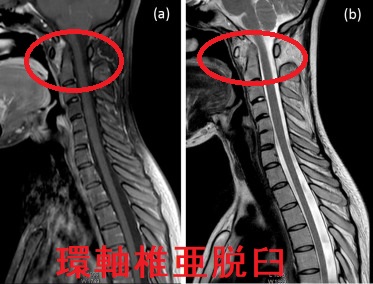

環軸椎亜脱臼

環軸椎亜脱臼は、第1頸椎(環椎)と第2頸椎(軸椎)を接合する環軸椎関節がずれて生じます。関節リウマチでは、環軸椎関節を接合する①環椎横靱帯の滑膜炎、②軸椎歯突起の破壊などにより環軸椎亜脱臼します。ダウン症候群でも環軸椎亜脱臼と甲状腺疾患の合併が多い[ダウン(Down)症候群と甲状腺の病気]。

環軸椎亜脱臼では、前屈位もしくは通常立位頸椎X線写真側面像の環椎歯突起間距離(atlantodental interval:ADI)が5 mm 以上になる(正常3 mm 以下)。後屈位でADIが正常範囲になる場合がある。